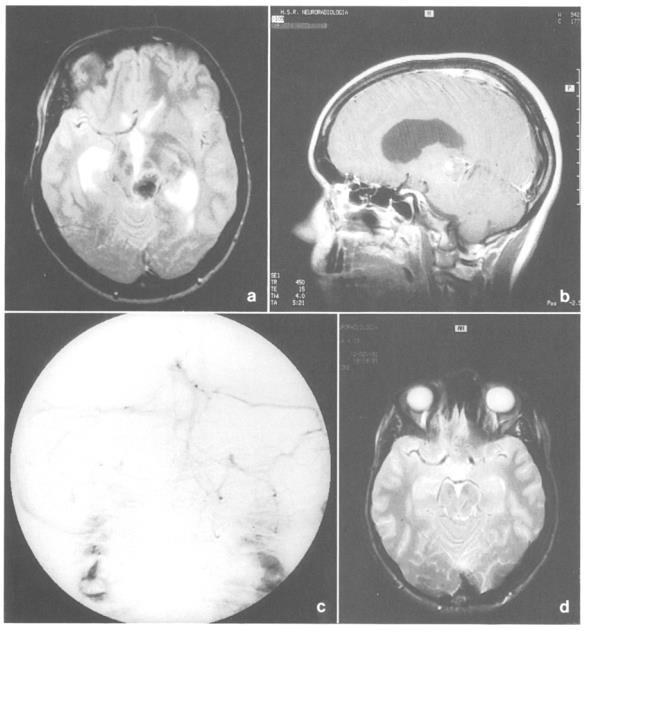

多形性胶质母细胞瘤(GBM)很少在松果体区发现。本文介绍了一个松果体区原发性胶质母细胞瘤(GBM)的病例,讨论了临床过程、影像学表现和治疗方法。根...

磁共振成像是优选的诊断技术,将海绵状血管瘤与的松果体区肿瘤区分开来。无需立体定向活检或术前盲照射。可以进行早期显微外科干预,预防复发性出...